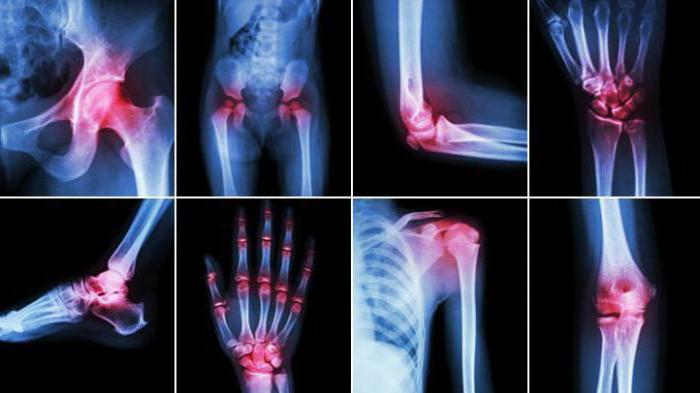

Симптомы

Недифференцированный артрит называют так потому, что в ходе его протекания может быть задет любой сустав организма, тогда как другие виды артрита бьют только по суставам в определенных зонах. Пораженные суставы распухают и воспаляются, становятся горячими на ощупь, может покраснеть кожа над ними. Появляются сильные болезненные ощущения. Движения становятся затрудненными и тоже причиняют боль.

Часто возникает лихорадка с ознобом и повышением температуры. Затем наступает деформация суставов, они искривляются, становятся узловатыми и частично или полностью теряют подвижность. Такая форма заболевания влечет за собой назначение инвалидности.